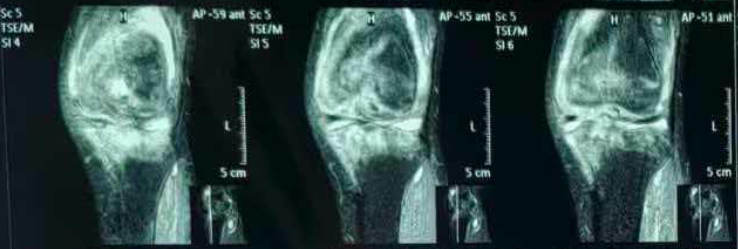

2月前,患者就诊于当地医院骨科,化验虎红平板凝集试验阳性,试管凝集试验:滴度≥1:160,PCR检测阳性。完善膝关节磁共振,在失状位可见:股骨、胫骨下斑片状、弥漫样高信号,提示骨髓水肿/炎性浸润(图1),股骨前方、股四头肌腱下方高信号,提示髌上囊积液(图2)。

图2. 股骨前方、股四头肌腱下方高信号,提示髌上囊积液